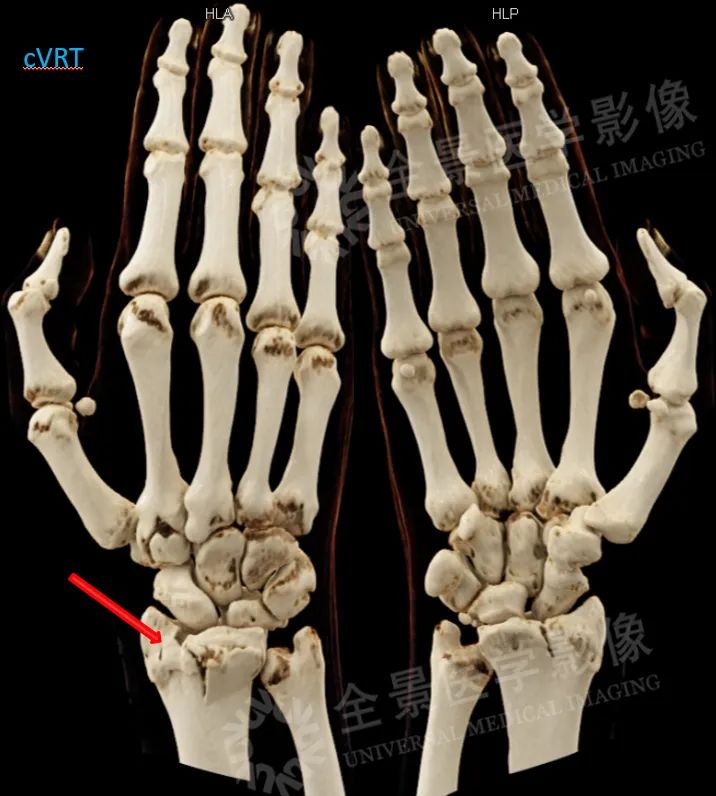

1.能够直观地显示骨折,对于骨肿瘤细节显示更为清晰;

案例:右侧桡骨远端粉碎性骨折,累及关节面;月骨多发撕脱骨折,伴舟月关节脱位可能

cVRT显示骨折线细节及骨碎片(红箭)。